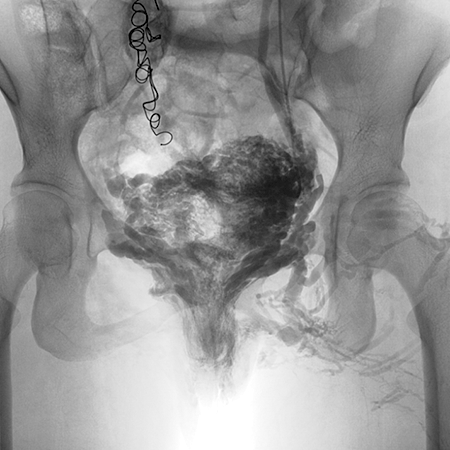

Ante la sospecha de SCP, se debe continuar el estudio realizando ecografía abdominal y transvaginal, dichos estudios nos aportan valiosa información, que nos orientan a la probable causa. No obstante, la confirmación diagnóstica se realiza mediante la flebografía pélvica, prueba que además permite realizar el tratamiento en el mismo momento.

El tratamiento consiste en la embolización que es la oclusión de esas venas enfermas con reflujo mediante depósito de coils (espirales metálicos). Esto se realiza durante la flebografía pélvica, mínimamente invasiva, con una punción en una vena del brazo que permite realizar tanto el diagnóstico como el tratamiento en el mismo acto.

ANTES

TTO SCP

DESPUÉS